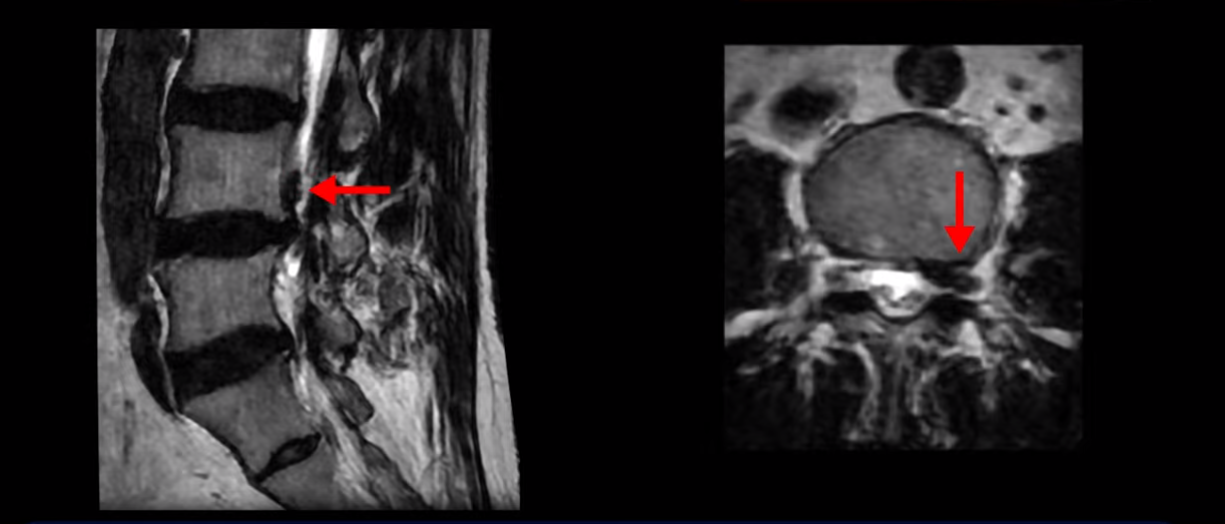

하지만 이분의 갑작스러운 통증을 일으키는 원인은 4번 5번에 발생한 디스크 파열입니다.

이분은 왼쪽 무릎 아래로 본인 표현으로는 다리를 잘라 버리고 싶다고 할 정도의 심한 통증이 있는데 보통 이런 표현은 디스크 파열이 발생했을 때 많이 사용하는 표현입니다. 이분 4번 5번 디스크를 자세히 보면 왼쪽으로 파열되어 밀려 올라간 디스크 수핵을 볼 수 있습니다.

옆에서도 보이지만 단면에서도 왼쪽으로 심하게 밀려나온 수핵이 잘 보입니다.